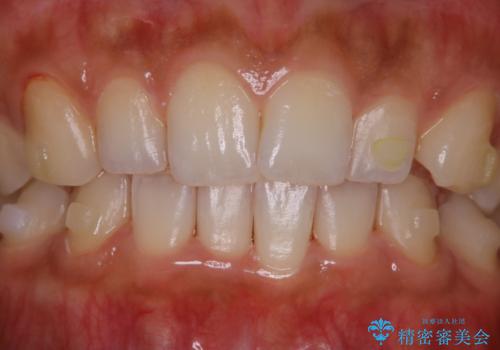

- インビザラインでの矯正治療中に、着色や汚れが気になるとのことでした。PMTC60分コースを行いました。

インビザライン治療中には、歯の表面にアタッチメント(効率的に歯の移動をするもの)を設定します。そのため歯ブラシでは届きにくい細かい部分などに、歯石や着色がついてしまうことがあります。着色などを放置していると、着色なのか、虫歯なのかの判別もしずらく正確にお口の中の状態を診断できません。

矯正治療中も定期的に歯科医院にてPMTCを受けて、お口のケアを行うことをおすすめします。